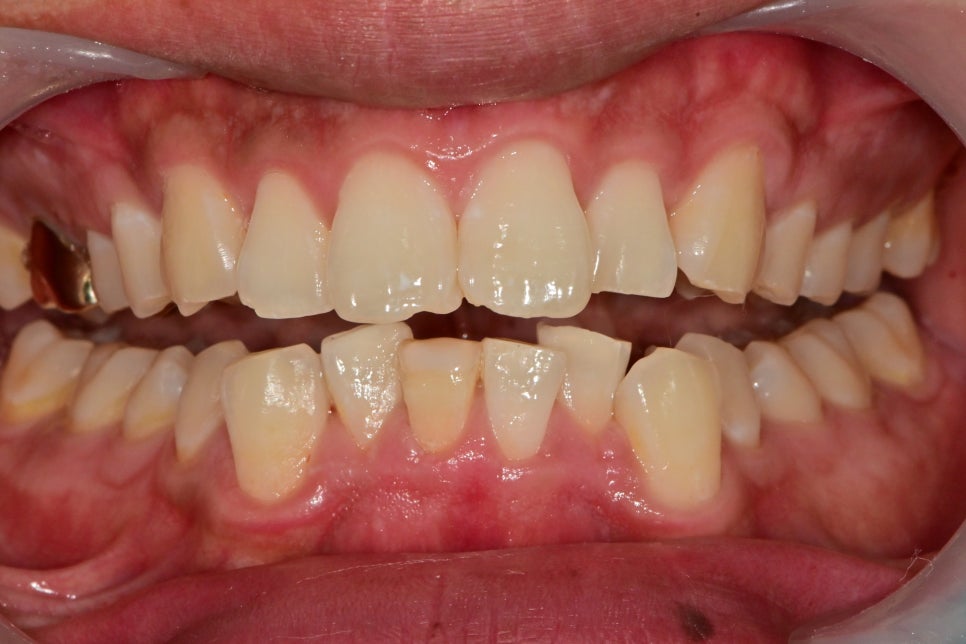

엑스레이 사진상에서 아래 앞니 뿌리 끝이 염증이 생긴 것을 확인할 수 있었습니다.

신경치료가 중단된 상태로 보이고, 치아 주변의 수복물은 오래되어 누출이 일어났을 것이고

주변 잇몸도 치석으로 인해 관리가 필요한 상태였습니다.

이 환자분 같은 경우는 치아의 크기가 작은 곳이고

치열이 고르지 않고 보철을 위해 치아를 다듬는 과정에서

남아있는 치아의 양이 너무 작아 파절의 위험성이 있기 때문에

주변 치아보다 신경치료를 한 치아는 색상이 어둡기 때문에